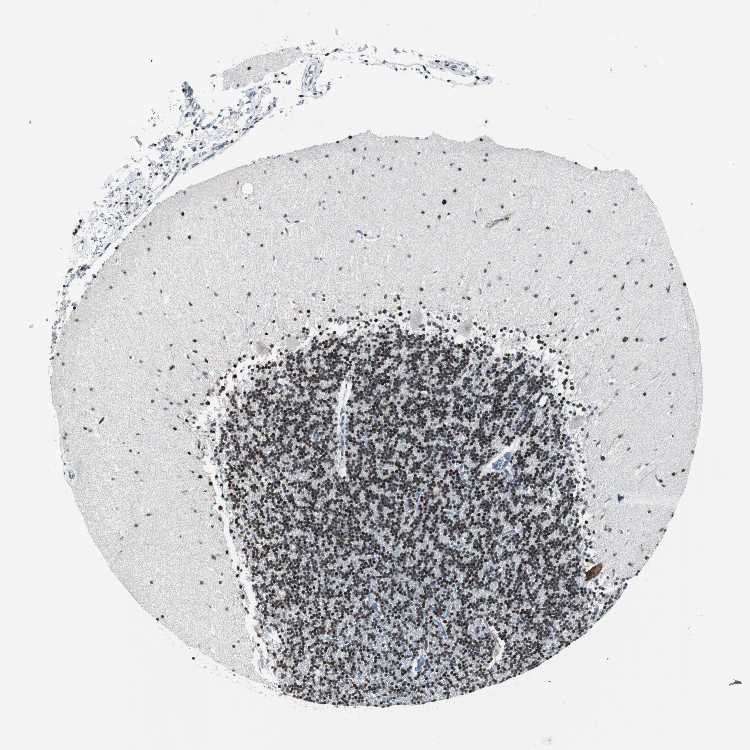

CEREBELLUM - Antibody stainingi

Antibody staining in the annotated cell types in the current human tissue is reported as not detected, low, medium, or high, based on conventional immunohistochemistry profiling in selected tissues. This score is based on the combination of the staining intensity and fraction of stained cells.

Each image is clickable and will lead to virtual microscopy that enables deeper exploration of all samples and also displays staining intensity scores, fraction scores and subcellular localization as well as patient and tissue information for each sample.

Antibody HPA005544Antibody CAB004508

Purkinje cells HighLow

Cells in granular layer -High

Cells in molecular layer LowMedium